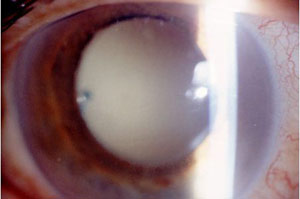

5. 玻璃體:玻璃體侵潤引起的混濁若能看到視網膜和血管,為輕度混濁。眼底紅光反射消失為重度混濁。

a. 丙酸菌屬眼內炎:炎症輕但持續存在,

b. 真菌感染:玻璃體腔內有珍珠樣或棉絮狀混濁,但眼底窺視較清晰。

c. 表皮葡萄球菌:玻璃體侵潤較輕,預後較好。

d. 其他革藍氏陽性球菌:如金葡菌、鏈球菌玻璃體侵潤較重,紅光反射常消失。膿性物常蔓延到視網膜下。預後差。